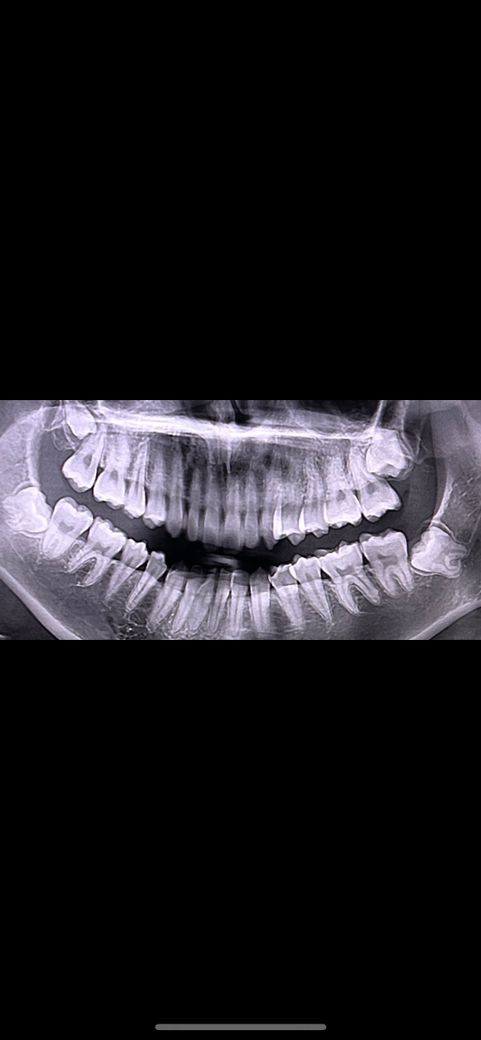

제가 다니는 치과에선 아프지 않은 이상 안뽑아도 된다고 하는데 맞을까요? 사진 중에 꼭 뽑아야하는 사랑니가 있는지 알려주세요!!

• 1번 째 사진

사진 상으로는 사랑니가 4개 존재합니다. 다만 모두 매복되어 있어 지금으로서는 큰 문제를 일으키지 않습니다. 추후에 문제가 되거나 부기 및 통증 등이 나타나는 쪽에만 사랑니 발치를 해도 무방해 보입니다.

4개 모두 매복사랑니이고 어느정도 옆 어금니를 누르고 있습니다. 이러한 경우에는 멀쩡한 옆 어금니(제2대구치)에 충치를 유발하거나 치근흡수를 시킬 수도 있습니다. 대학병원에서도 한번 진단을 받아보시기 바랍니다.